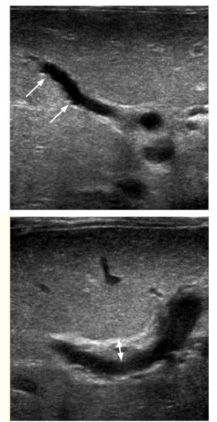

胆道闭锁是发生于婴儿时期的严重肝胆疾病,表现为进行性加重的梗阻性黄疸。本病特点是肝纤维化发生早、进展快、程度重,很快进展为肝硬化。临床症状包括皮肤和巩膜黄染、大便颜色变浅(陶土便)、尿色加深(浓茶色),延迟诊断的患儿可能出现凝血功能异常、腹水、脾大、上消化道出血、肝脏功能衰竭等终末期肝病表现。最便捷的筛查手段即观察婴儿大便颜色,棕色、黄色、绿色便为正常颜色变,而灰白、浅黄、黄白色便为异常颜色便(图1)。如果发现婴儿大便颜色异常,同时有黄疸表现,应积极进行血生化检查,了解总胆红素和直接胆红素水平,明确有无梗阻性黄疸表现。大便的颜色可以参照大便比色卡进行对比(图2)。明确有梗阻性黄疸的患儿,下一步考虑进行腹部超声检查,了解有无肝脏实质回声增粗、肝脏肿大、肝脏被膜下血流征、肝门部纤维块三角征(图3)、胆囊瘪小萎缩并餐后无收缩等胆道闭锁特征性超声表现,进行肝脏硬度测量了解有无肝脏纤维化、硬化,进行血清MMP-7检查了解有无水平增高,由此初步评价是否倾向胆道闭锁诊断。对于部分鉴别诊断困难的患儿,在完善基因筛查排除遗传代谢病的同时,进行短时间(3-7天)试验性保肝利胆治疗,同时筛查病毒感染情况并进行抗病毒治疗(巨细胞病毒等),密切观察保守治疗效果。治疗效果欠佳者,积极进行手术探查,通过术中观察肝脏胆囊外观和胆囊内胆汁颜色(图4)、胆道造影、肝脏病理活检等手段,最终明确诊断,不宜过久进行保守治疗。

图3 超声胆囊瘪小、肝门部纤维块三角征